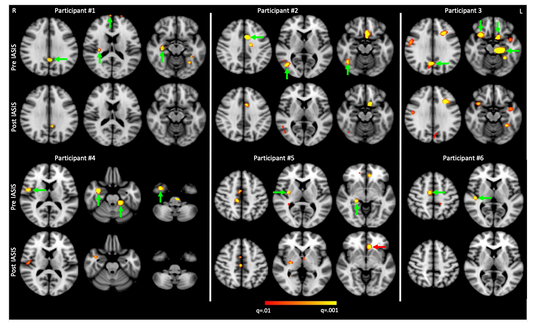

Treatment Study: IASIS reduced abnormal slow wa...

In this treatment study, IASIS Micro Current Neurofeedback reduced abnormal slow waves in six TBI patients. See the full study here.